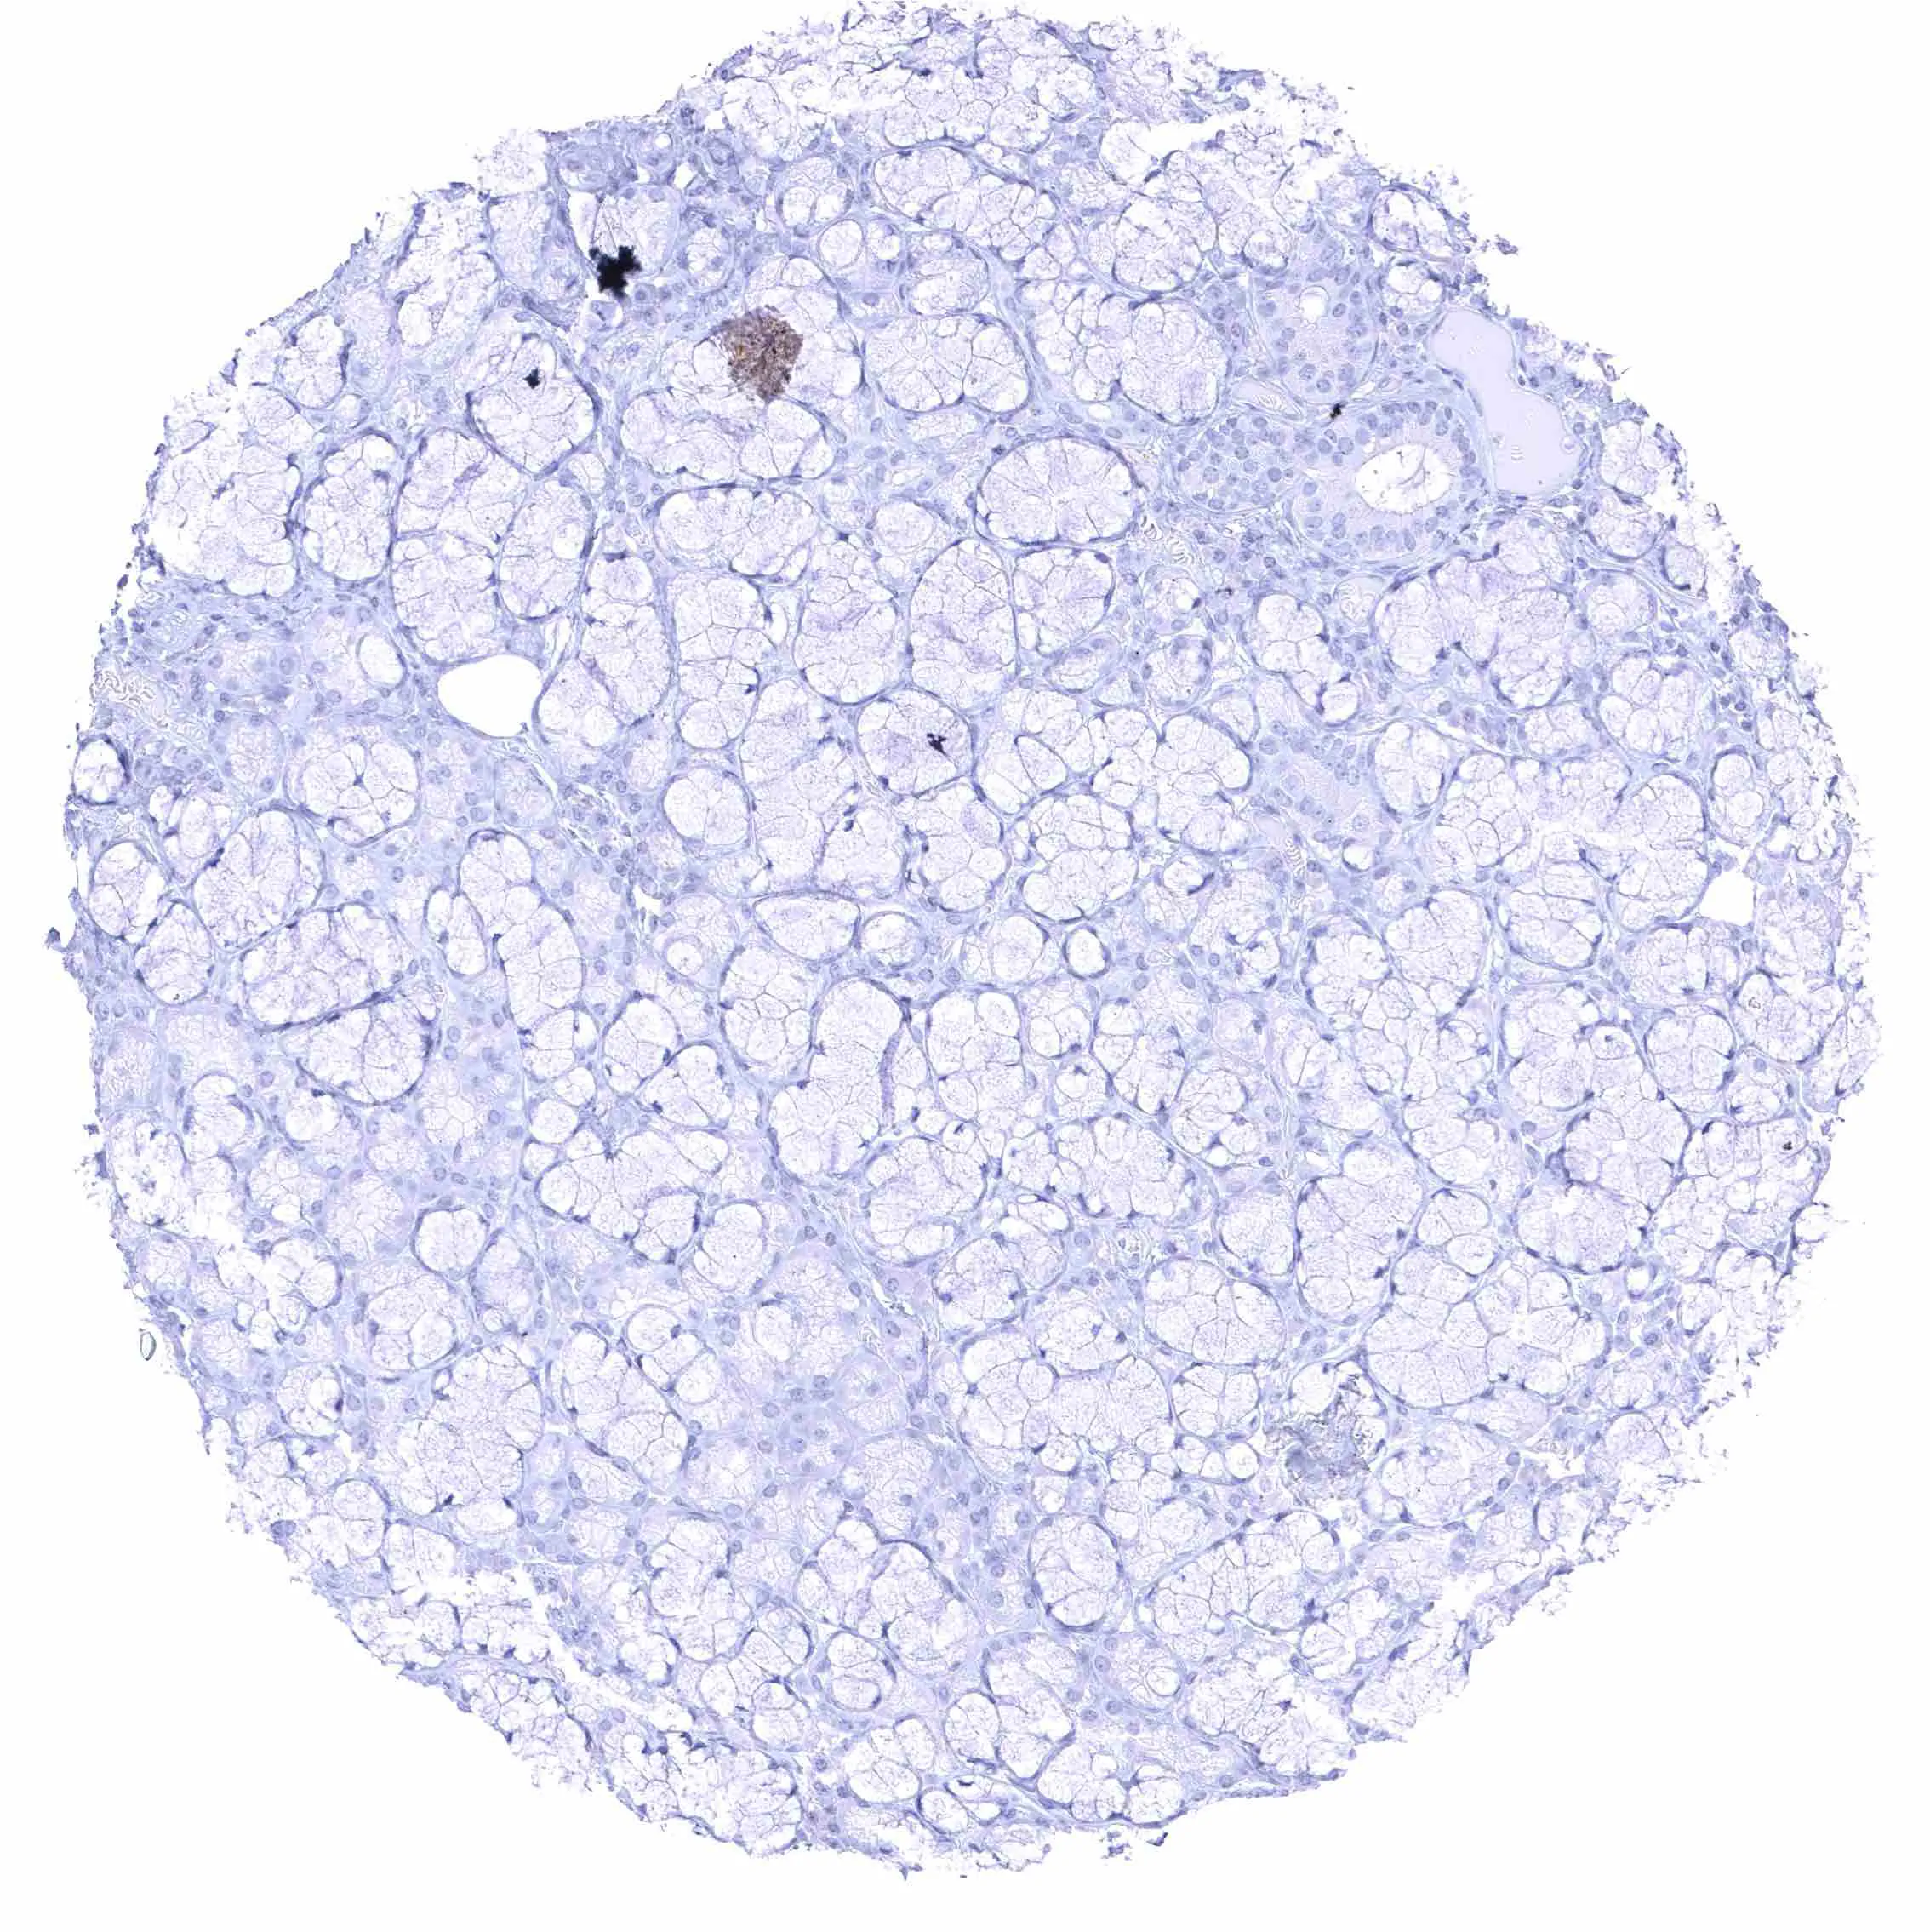

Fat